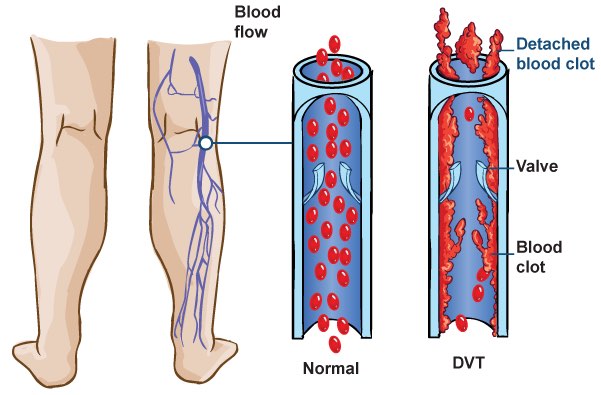

Overview

Package includes:

Days in hospital : 2 to 3 Days (For patient and one attendant)

Days in hotel : 3 Days (For patient and one attendant)

Room type in hospital : Shared

Room type in hotel : Private

Hotel category: Standard

Value added benefits of the Thrombosis:

Ø Doctor consultation charges

Ø Lab tests and diagnostic charges

Ø Room charges inside hospital during the procedure

Ø Surgeon Fee

Ø Nursing charges

Ø Hospital surgery suite charges

Ø Anesthesia charges

Ø Routine medicines and routine consumables (bandages, dressings etc.)

Ø Food and Beverages inside hospital stay for patient and one attendant.

Extra benefits:

ü Interpreter

ü Visa assistance

Ø Site tourism of the city

Ø Follow up with the doctor

Ø Airport pick up and drop

Ø Free online consultation with the doctor

Ø Priority appointments with the doctor

Ø Room upgrade from sharing to private